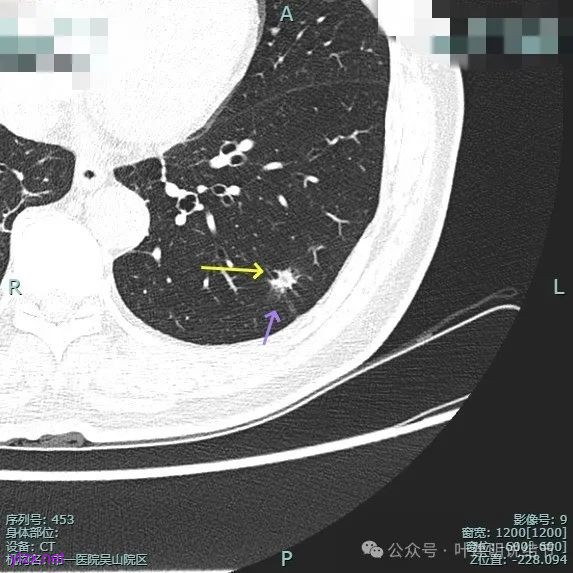

整体纵向仍偏长条些,实性部分不太致密,边上磨玻璃成分的轮廓与界限不太清楚,毛刺显得长。

仍有支气管扩张,但较2024年时密度感觉低了点。

密度较淡且缺乏收缩力。

密度杂乱,血管进入,但血管说不上明显异常增粗,磨玻璃成分淡而瘤肺界限欠清。

总体较之前密度有减低,缺乏聚拢性。

我考虑较前好转,应该是慢性炎,建议9个月后再复查。